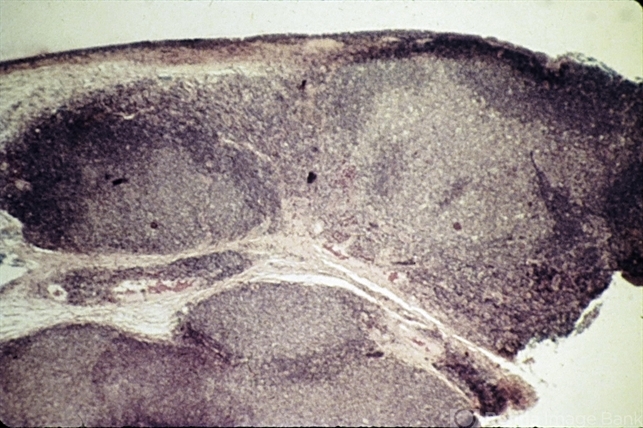

- lymph node, hyperplasia, conjunctiva

- Benign lymphoid hyperplasia of the conjunctiva may resemble a normal lymph node.